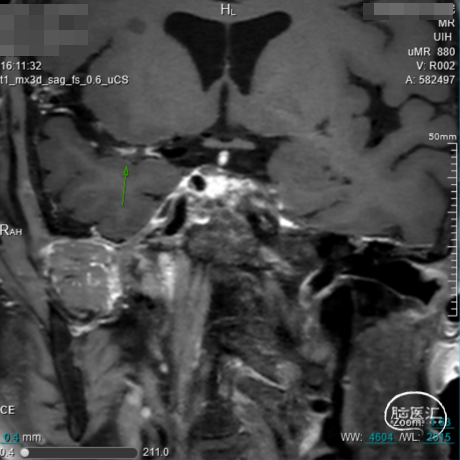

术前影像学检查

➢术前HMRI